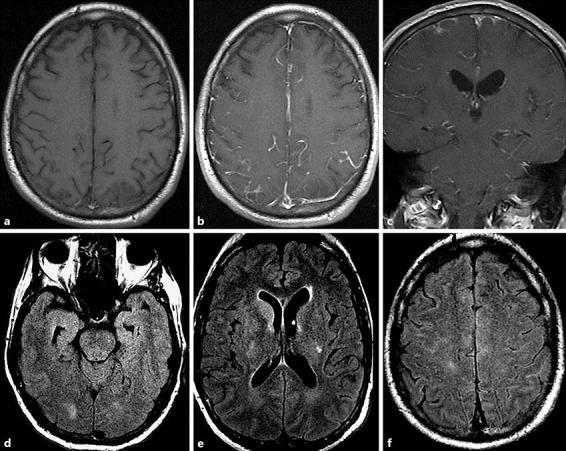

We report the case of a 63-year-old male diagnosed with chronic autoimmune mediated meningoencephalitis and periodic cyclical fever syndrome. After 2 years of failed conventional treatment and recurrent hospitalizations, anakinra treatment (an interleukin-1 [IL-1] receptor antagonist) was trialed which resulted in full recovery. As evidenced by this case, anakinra can be used to treat chronic autoimmune meningitis, which can often be refractory to treatment.

我们报告了一例63岁男性患者,诊断为慢性自身免疫介导的脑膜脑炎和周期性循环发热综合征。在传统治疗失败且反复住院2年后,试用了阿那白滞素治疗(一种白细胞介素-1 [IL-1] 受体拮抗剂),结果患者完全康复。以此病例为证,阿那白滞素可用于治疗慢性自身免疫性脑膜炎,而这种疾病通常治疗困难。